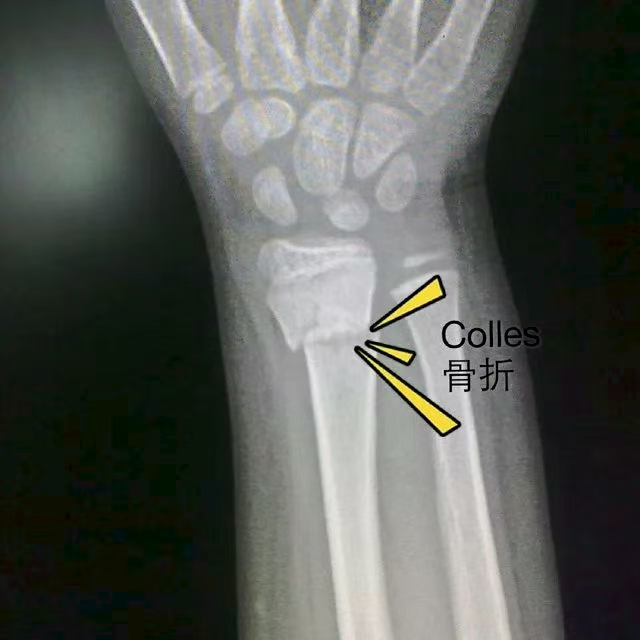

季大国首先表明了自己是宿迁市一家医院的急诊科医生,并开始对老人进行检查。经询问得知,老人是在摔倒时下意识用手掌撑地所致。根据老人手腕呈现的典型“餐叉样”畸形外观,季大国判断其伤情为桡骨远端骨折,即临床上常见的“柯力氏骨折”。

什么是“柯力氏骨折”?

“柯力氏骨折”(Colles' Fracture)是骨科最常见的骨折之一,指桡骨远端(靠近手腕的一端)发生的骨折。

如何发生:多见于摔倒时,身体倒地瞬间用手掌撑地,导致暴力通过手掌传导至腕部,引起桡骨骨折。

典型特征:受伤手腕从侧面看会呈现出类似餐叉背面的畸形,并伴有剧烈疼痛、肿胀和活动受限。